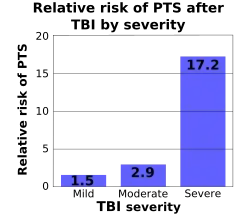

Movement disorders that may develop after TBI include tremor, ataxia (uncoordinated muscle movements), spasticity (muscle contractions are overactive), myoclonus (shock-like contractions of muscles), and loss of movement range and control (in particular with a loss of movement repertoire).[89][147] The risk of post-traumatic seizures increases with severity of trauma (image at right) and is particularly elevated with certain types of brain trauma such as cerebral contusions or hematomas.[138] People with early seizures, those occurring within a week of injury, have an increased risk of post-traumatic epilepsy (recurrent seizures occurring more than a week after the initial trauma).[148] People may lose or experience altered vision, hearing, or smell.[11]